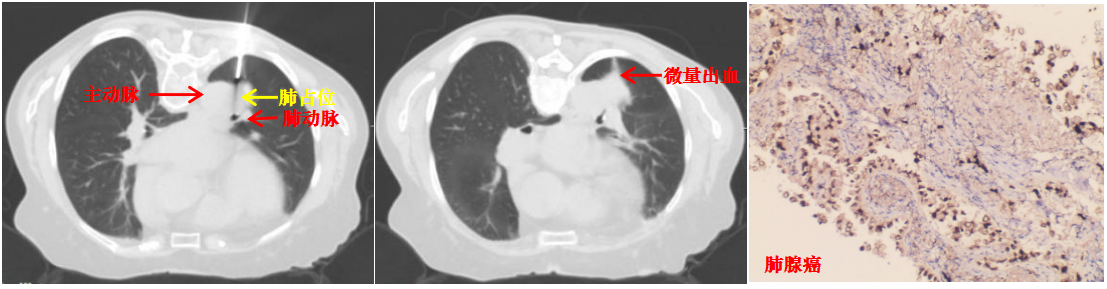

本病例患者肺结节穿刺中(左图)、穿刺后(中图)和病理诊断(右图)

面对诊疗压力与家属的殷切期盼,陆霓虹主任带领呼吸介入团队开展周密术前讨论,反复对患者CT影像进行三维重建和多角度研判,精密测算进针点、角度及深度。同时,针对术中可能出现的咯血、气胸、空气栓塞等并发症,制定了严密的“阶梯式”应急方案。主管医师吴文娟博士及赵思蓉医师用通俗易懂的方式讲解穿刺方案,最终打消了家属的不安与疑虑。

取得患者及家属同意后,陆霓虹主任带领介入团队医生杨嫄、贺晓洁,护士杨红艳、王丽,在CT引导下实施穿刺活检。影像监控下,针尖精准抵达病灶核心,实时测量显示针尖距离主动脉仅4mm,团队迅速完成切割取材,仅出现极少量创面出血,对症处理后患者安返病房,无出血、气胸等并发症。

术后病理确诊为肺腺癌,为患者后续治疗提供了决定性依据。此次技术突破,是科室在高危肺结节诊疗领域的又一跨越。未来,财神捕鱼 呼吸与危重症医学科介入团队将持续精进技术、优化诊疗流程,为更多高危肺结节患者提供精准、安全的微创诊疗服务。